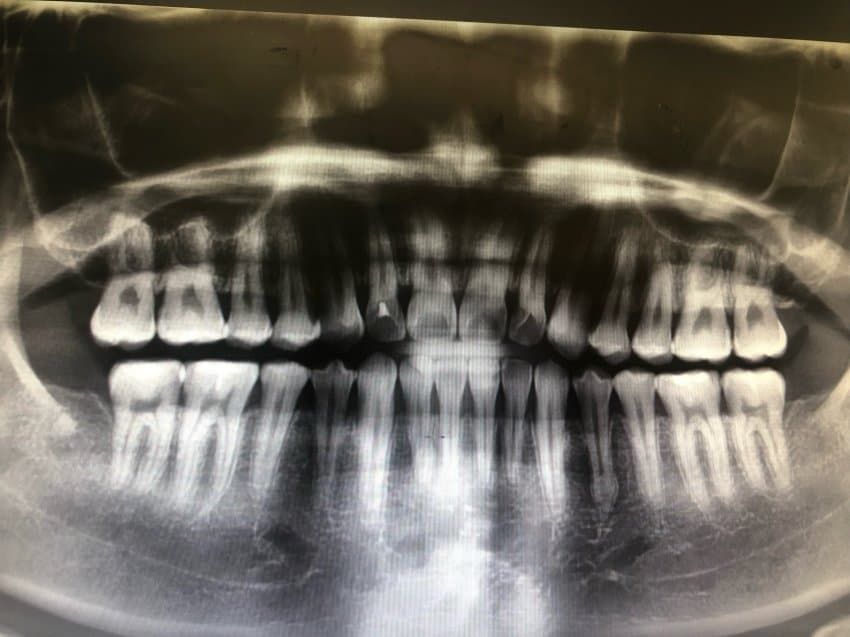

어금니 교모가 심하면 문제가 되나요?

우측 하단 어금니가 위 어금니랑 교합이 잘 안맞아서

교모가 심하다고 하는데 어떤 문제가 되나요? 그리고 앞으로 어떻게 해야될까요?

교모를 유발하는 원인이 개선되지 않으면 치아가 더 마모되어 시릴 수 있고 깨져나갈 수도 있습니다 또한 부정교합이 유발되거나 턱관절 질환이 유발될 수 있습니다 원인을 먼저 찾아보세요